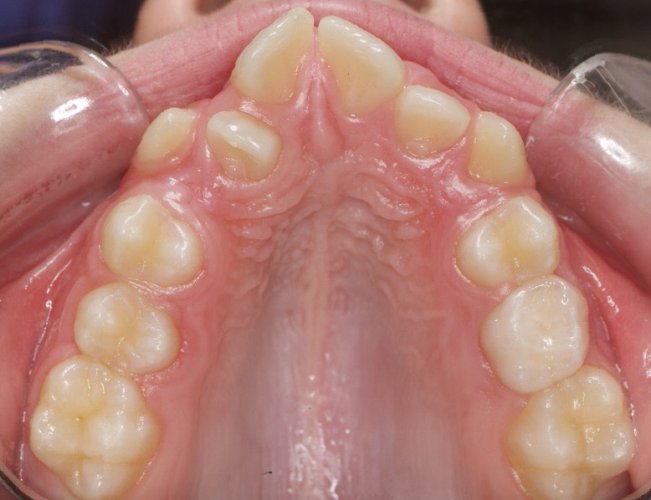

Un “diastema” es una separación extraordinariamente grande entre dos o más dientes. La mayoría de las veces, el diastema aparece entre los dos dientes delanteros superiores. Muchos niños tienen diastema cuando se les caen los dientes de leche, pero en la mayoría de los casos esta distancia desaparece cuando salen los dientes permanentes.

Los diastemas pueden deberse a una diferencia en los tamaños de los dientes, a la falta de algún diente o a que el frenillo labial sea demasiado grande. El frenillo labial es el tejido que va desde el interior del labio hasta la encía, en el lugar donde se sitúan los dos dientes delanteros superiores. Los diastemas también pueden deberse a problemas en la alineación de la boca, como la sobremordida horizontal o la protrusión de los dientes1.